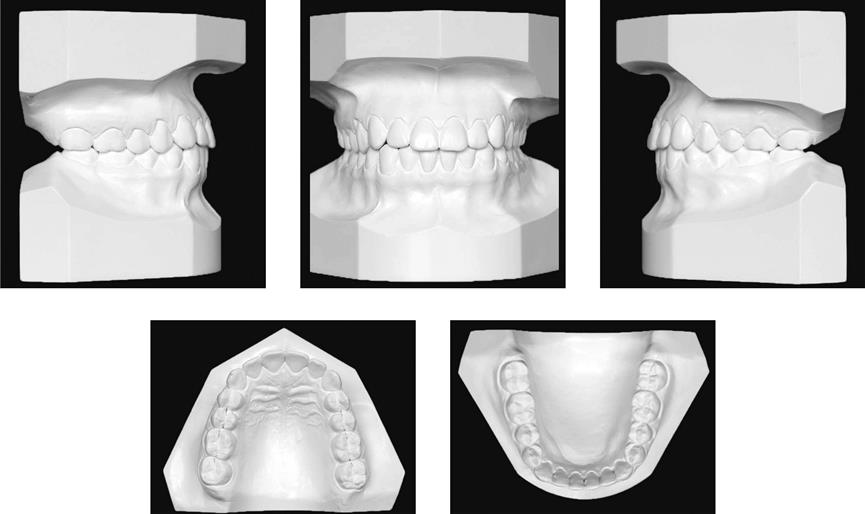

Modelos

Son copias en yeso de los dientes y huesos maxilares que al colocarse en posición reproducen la mordida habitual del paciente. Con estos modelos el ortodoncista estudia la forma y tamaño de los dientes y de los arcos dentarios con índices, que le darán la información necesaria para el diagnóstico.